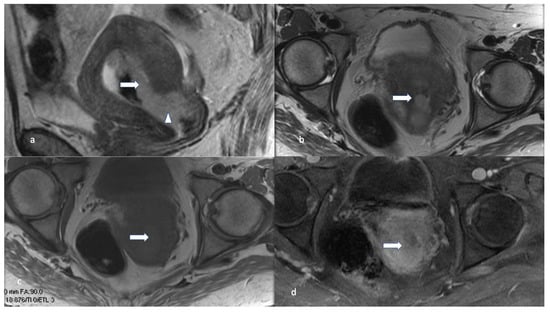

5.3. Magnetic Resonance Imaging (MRI)